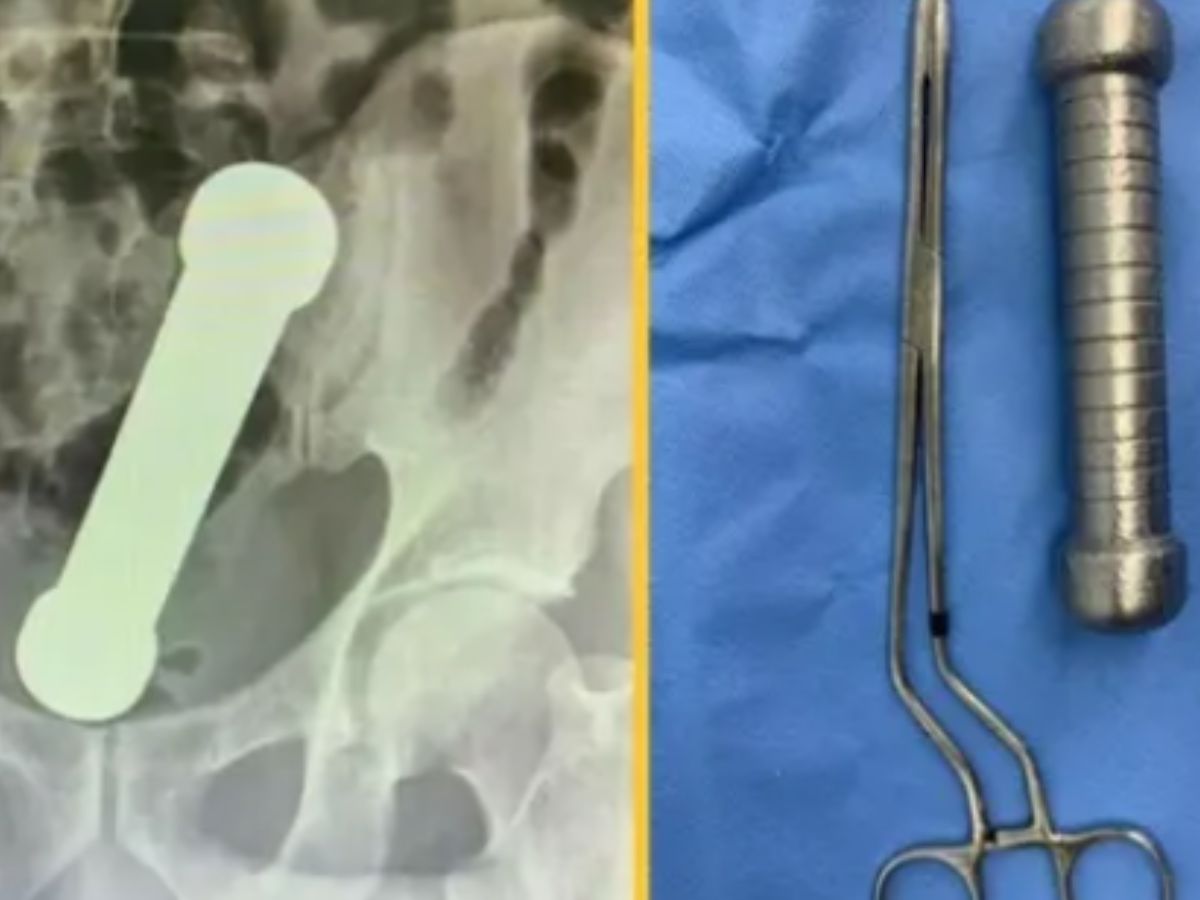

A shocking Brazilian medical case published in the International Journal of Surgery Case Reports found that a 54-year-old man was brought into the hospital with a 2 kg dumbbell in his rectum. He presented with abdominal pain, nausea, and constipation for two days prior before coming in.

Imaging examinations revealed that the gym equipment was lodged in the rectosigmoid area, the junction of the rectum and colon. This site rendered removal especially risky and tricky due to poor access and risk of damage to adjacent tissues.